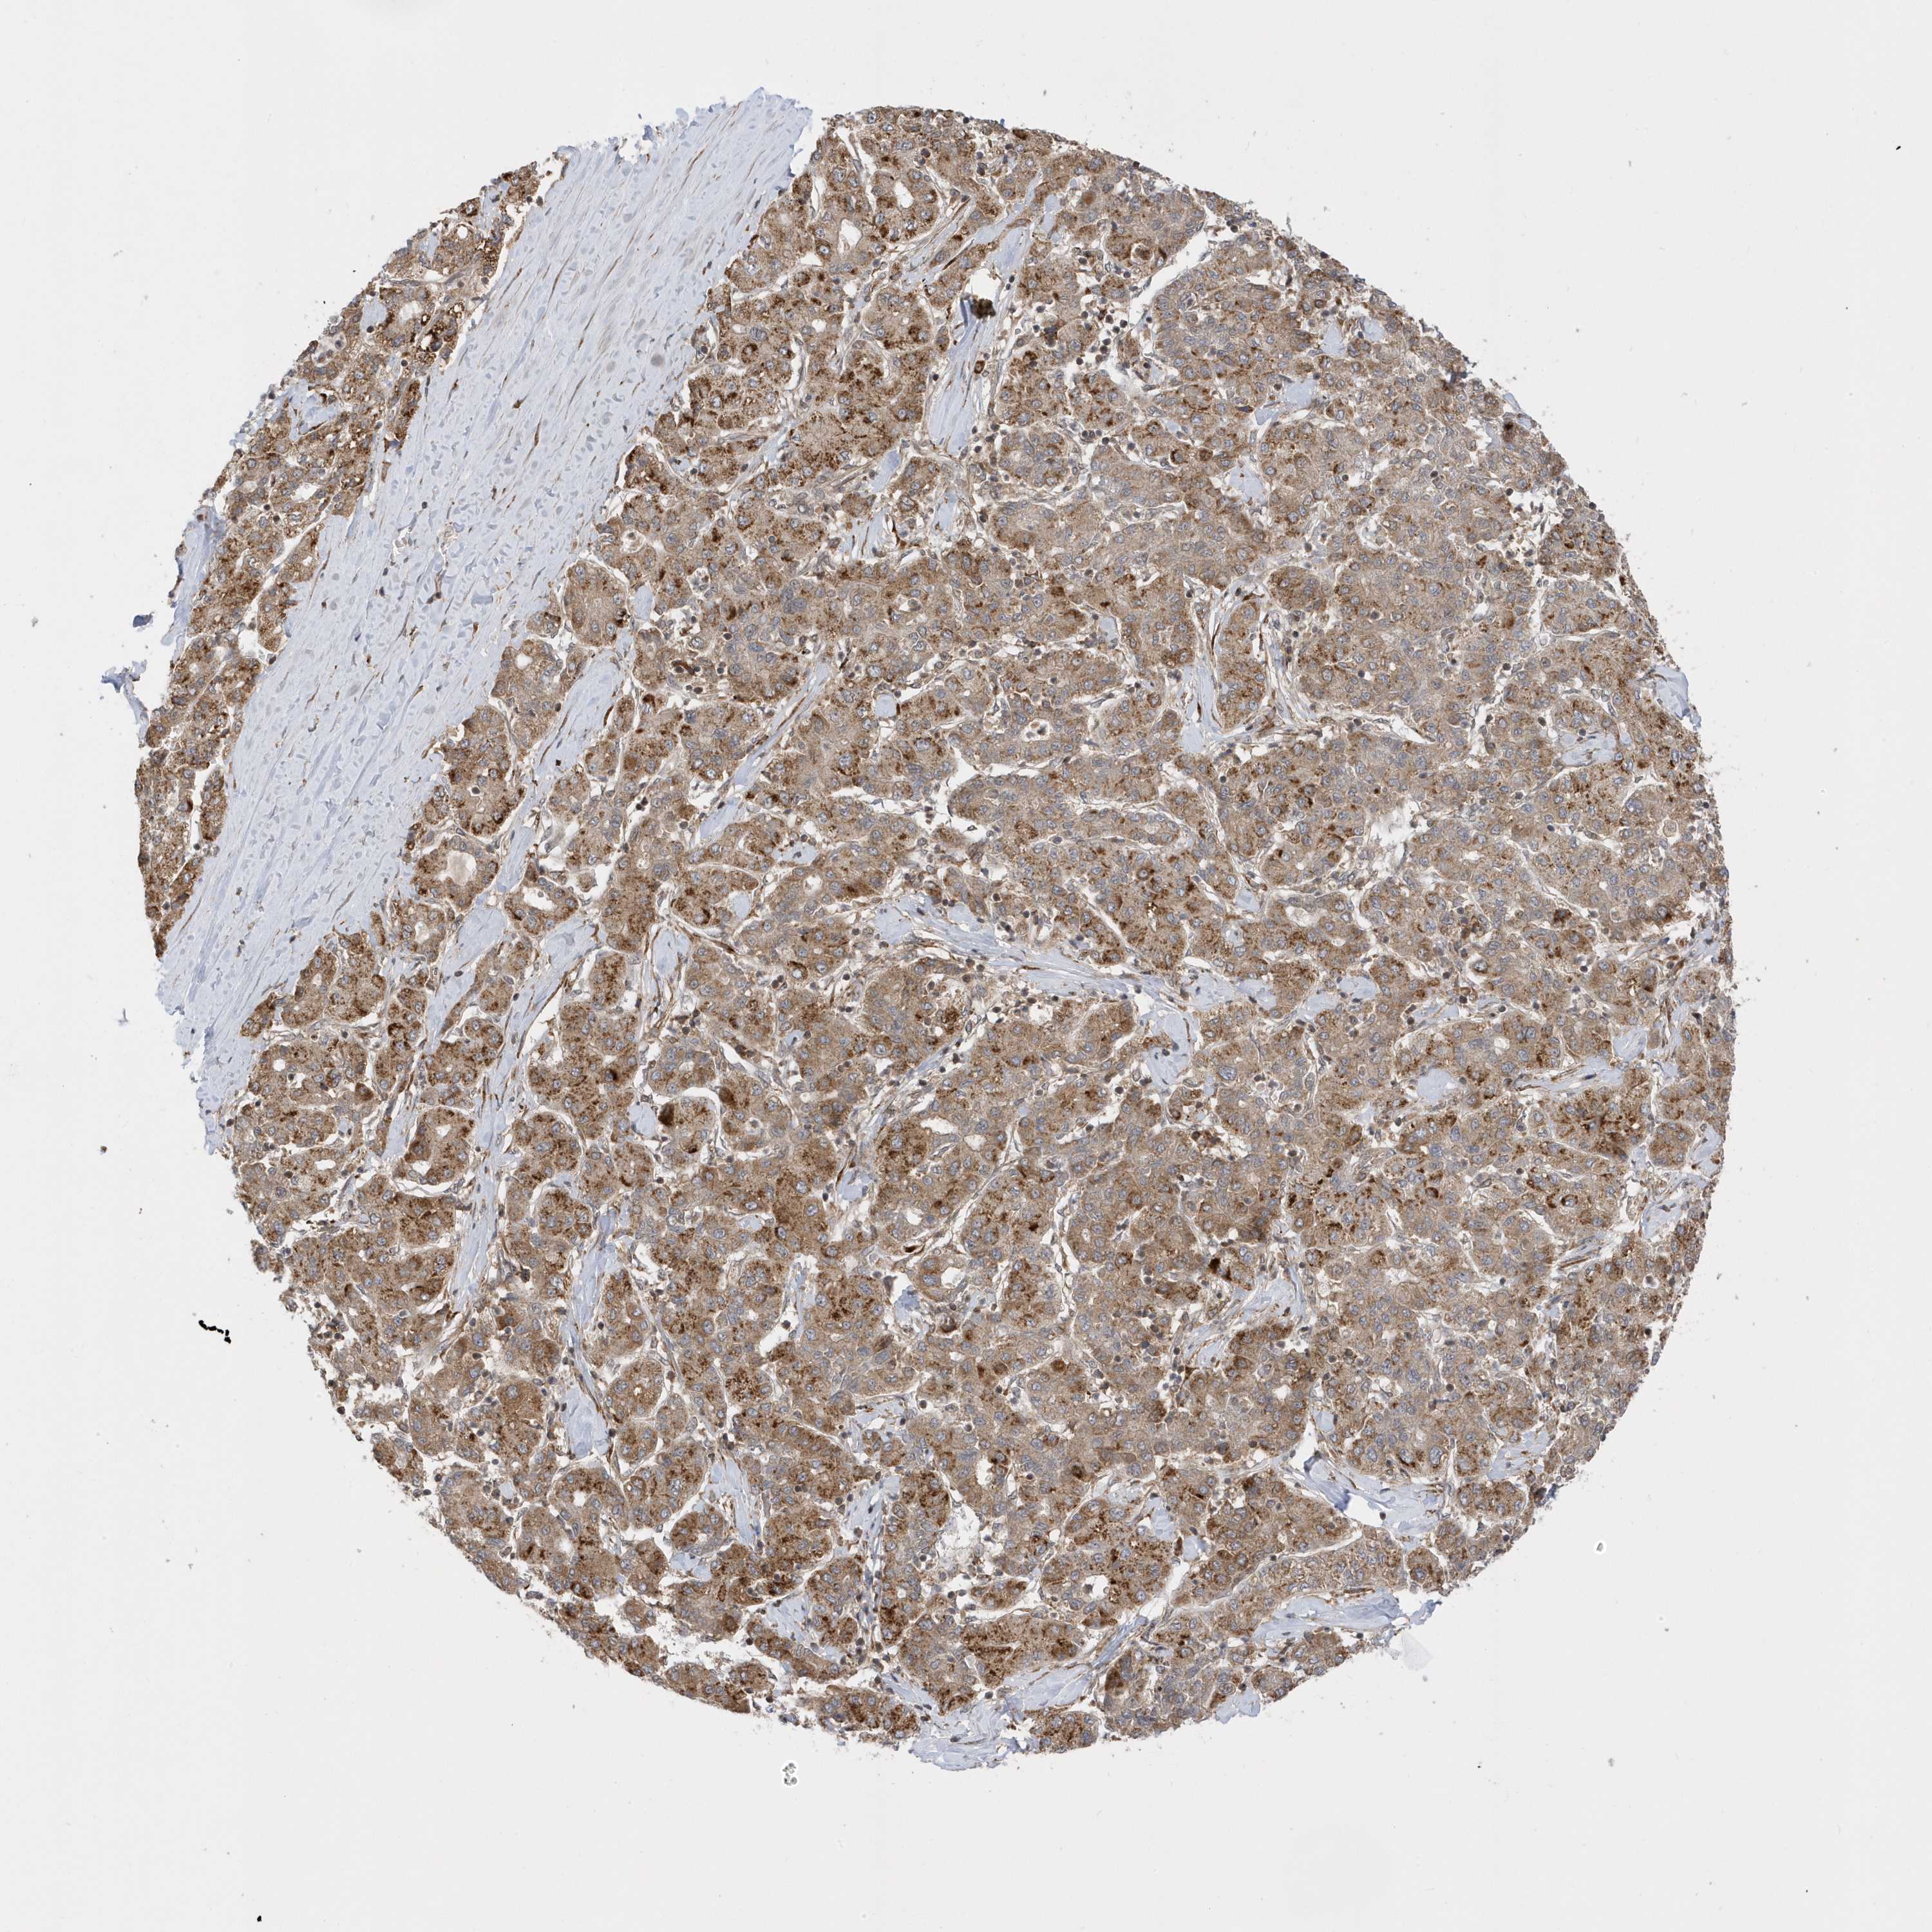

LIVER CANCER - Protein expressioni

A mouse-over function shows sample information and annotation data. Click on an image to view it in a full screen mode. Samples can be filtered based on level of antibody staining by selecting one or several of the following categories: high, medium, low and not detected. The assay and annotation is described here.

Note that samples used for immunohistochemistry by the Human Protein Atlas do not correspond to samples in the TCGA dataset.

Antibody stainingi

Antibody staining in the annotated cell types in the current human tissue is reported as not detected, low, medium, or high, based on conventional immunohistochemistry profiling in selected tissues. This score is based on the combination of the staining intensity and fraction of stained cells.

Each image is clickable and will lead to virtual microscopy that enables deeper exploration of all samples and also displays staining intensity scores, fraction scores and subcellular localization as well as patient and tissue information for each sample.

Antibody HPA034712

Staining

High

Medium

Low

Not detected

Intensity

Strong

Moderate

Weak

Negative

Quantity

>75%

75%-25%

<25%

None

Location

Nuclear

Cytoplasmic/membranous

Cytoplasmic/membranous,nuclear

Cholangiocarcinoma

Carcinoma, Hepatocellular, NOS